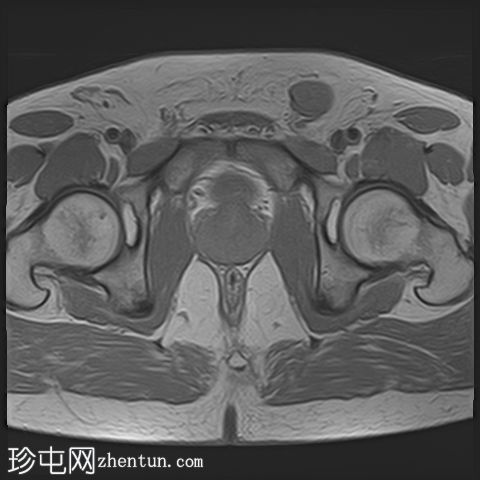

2.png

轴位T1加权像

脂肪抑制像

龟头可见不规则形状的软组织肿块,增强后明显强化,并伴有扩散受限。该肿块侵犯尿道海绵体,导致远端尿道狭窄和上游尿道扩张。

左侧腹股沟可见多个肿大的病理性淋巴结,右侧可见较小的非特异性淋巴结。

病理报告:阴茎活检显示浸润性鳞状细胞癌,分化不良,具有基底样特征。免疫组化标记物p63、CK5/6和P16均呈阳性,提示为HPV相关亚型。